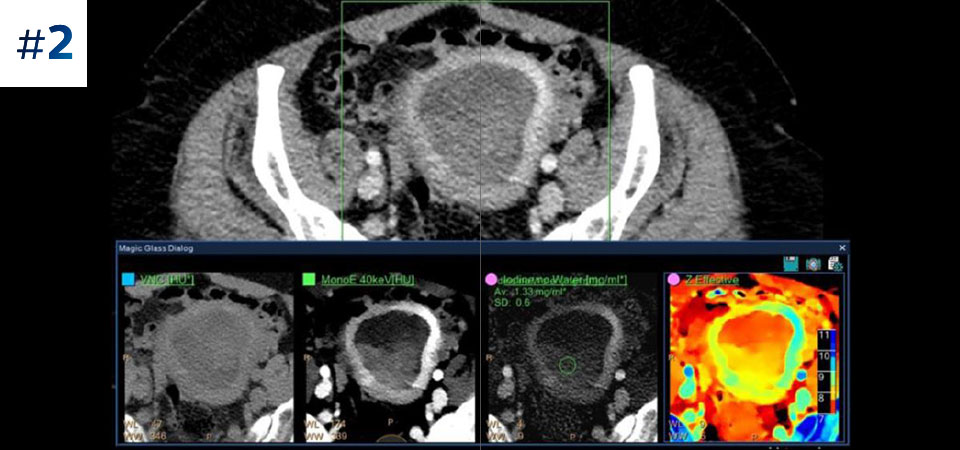

Pełna dostępność Pełne dane spektralne w każdym momencie zapewniają dostęp do wyników na każde żądanie – nawet w ujęciu retrospektywnym.

Ograniczenie liczby ponownych badań Udoskonalona charakterystyka i wizualizacja tkanek może ograniczyć konieczność wykonywania ponownych badań, jaka zachodzi w przypadku badań o niezadowalającej jakości oraz przypadkowych obserwacji.

Typowy przebieg badania Pojedyncze skanowanie zapewniające szybki dostęp do konwencjonalnych i spektralnych danych uzyskanych z użyciem niskiej dawki — za każdym razem i w przypadku każdego pacjenta.

Nie ograniczaj się do konwencjonalnej tomografii komputerowej. Zobacz, jak wyniki uzyskane dzięki warstwom detektora spektralnego mogą zwiększyć pewność diagnostyczną.

Zobacz różnicę pomiędzy tomografią komputerową opartą na detektorze spektralnym a konwencjonalną tomografią komputerową